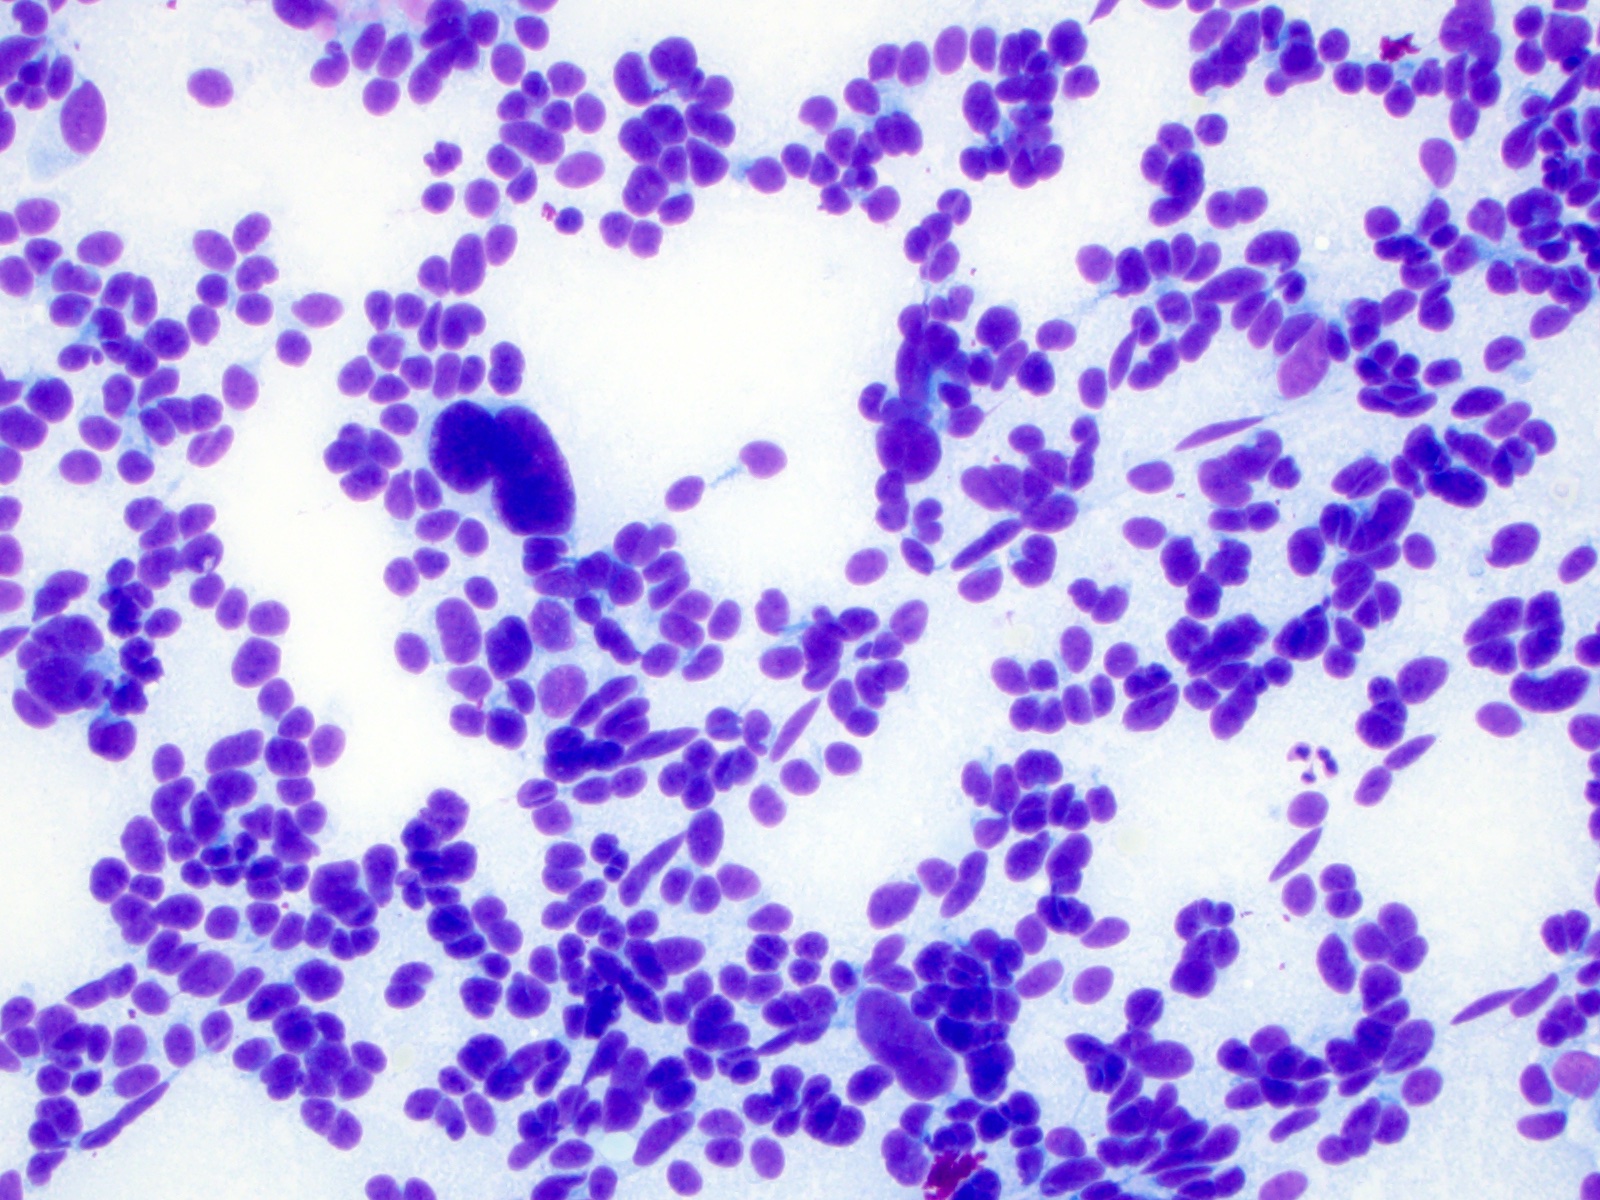

Cytology description

- Cellular specimen with round, ovoid, plasmacytoid or spindle cells singly or in small cluster; cells have abundant cytoplasm and eccentric nuclei; chromatin has salt and pepper appearance

- May have pink azurophilic granules and intranuclear pseudoinclusions; amyloid present occasionally (Am J Clin Pathol 1984;82:552)

- Paraganglioma-like variant:

- Predominantly ovoid to spindled epithelial cells in cohesive three dimensional clusters with sharp margins, rare isolated individual cells, no background colloid or amyloid

- Tumor cells have inconspicuous cytoplasm, significant nuclear atypia with occasional bizarre or binucleated cells, coarse and granular nuclear chromatin with occasional grooves and intranuclear inclusions (Cytopathology 2009;20:188)

Cytology images

Contributed by Ayana Suzuki, C.T. and Shuanzeng Wei, M.D., Ph.D.